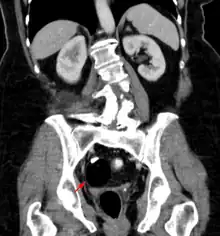

Diagnosis

Teratomas are thought to originate in utero, so can be considered congenital tumors. Many teratomas are not diagnosed until much later in childhood or in adulthood. Large tumors are more likely to be diagnosed early on. Sacrococcygeal and cervical teratomas are often detected by prenatal ultrasound. Additional diagnostic methods may include prenatal magnetic resonance imaging. In rare circumstances, the tumor is so large that the fetus may be damaged or die. In the case of large sacrococcygeal teratomas, a significant portion of the fetus' blood flow is redirected toward the teratoma (a phenomenon called steal syndrome), causing heart failure, or hydrops, of the fetus. In certain cases, fetal surgery may be indicated.

Beyond the newborn period, symptoms of a teratoma depend on its location and organ of origin. Ovarian teratomas often present with abdominal or pelvic pain, caused by torsion of the ovary or irritation of its ligaments. A recently discovered condition where ovarian teratomas cause encephalitis associated with antibodies against the N-methyl-D-aspartate receptor antibody (NMDAR) - often referred to as "anti-NMDA receptor encephalitis", was identified as a serious complication. Patients develop a multistage illness that progresses from psychosis, memory deficits, seizures, and language disintegration into a state of unresponsiveness with catatonic features often associated with abnormal movements, and autonomic and breathing instability.[33] Testicular teratomas present as a palpable mass in the testis; mediastinal teratomas often cause compression of the lungs or the airways and may present with chest pain and/or respiratory symptoms.